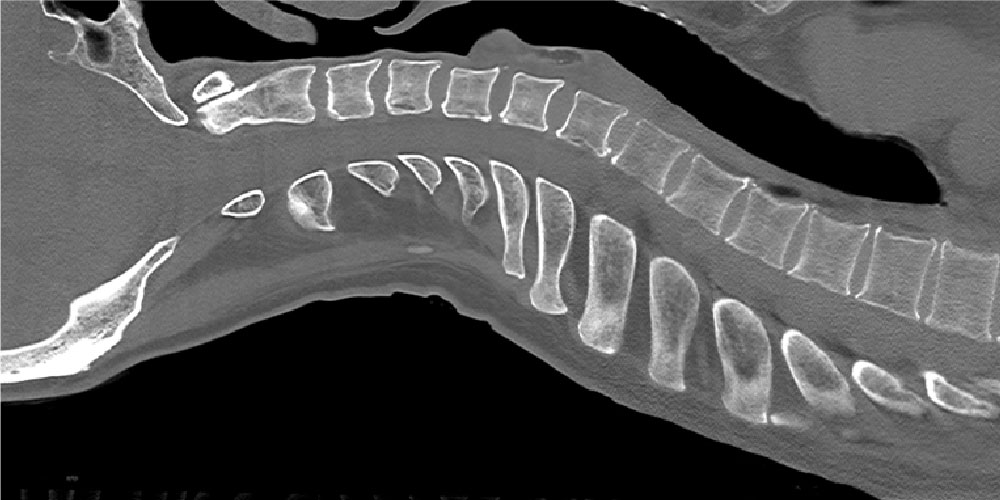

脊椎が正しいアーチを描くように首と背中の隙間を

埋めることで、

筋肉に余計な負荷がかからず

首や肩にかかる負担の軽減につながる。

脊椎・脊髄外科の権威と共に

理想的な背骨のアーチを

描く形状を追求。

首や肩の負担を軽減するには、背骨が理想的な

アーチを描いた状態で、

筋肉に余計な負荷が

かからないことが重要でした。

私たちは、脊椎・脊髄外科の権威と共に

幾度となく検証を繰り返し、

理想的な背骨のアーチを描くために

最適な形状を追求。

かからないように、頭から背中までを支える

理想的な形状にたどり着きました。